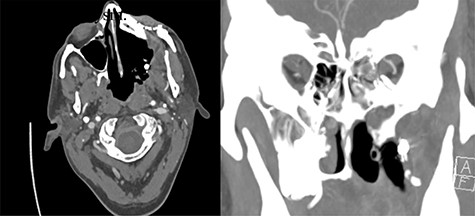

Eight months after treatment completion, the patient removed a small wire from his maxillectomy cavity that was consistent with a vascular coil from his previous IMA embolization. CT angiography was obtained notable for partial coil extrusion from a left IMA branch, with a separate vascular blush concerning for pseudoaneurysm of another IMA branch (Fig. 1). Several days later, he developed left-sided epistaxis, which was controlled with nasal packing and subsided after approximately 30 minutes. This was felt to represent a possible sentinel bleed; although his ECA was ligated proximally, there was thought to be sufficient backflow to fill the pseudoaneurysm and cause symptomatic bleeding, as has been reported previously [3].

Evidence of partially extruded embolization material within the left infratemporal fossa along the left maxillectomy defect in axial (left) and coronal (right) sections. Coronal view also demonstrates more inferior contrast blush concerning for pseudoaneurysm.